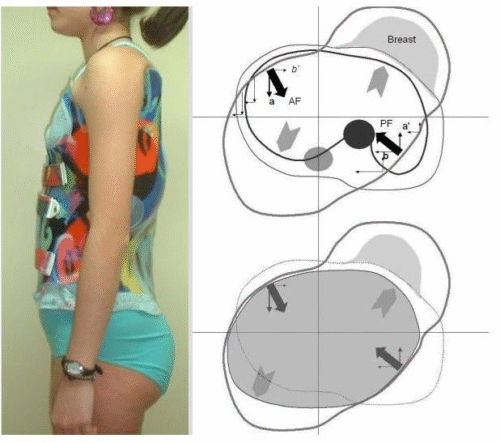

التطور الكبير في تصميم الأحزمة الطبية جعل علاج اعوجاج العمود الفقري عند المراهقين أكثر نجاحًا وأقل إزعاجًا. باستخدام تقنيات التصوير الثلاثي الأبعاد والمحاكاة الرقمية، أصبح الحزام أكثر خفة وراحة، ويعطي نتائج أفضل في تصحيح الانحناء والتواء العمود الفقري.

الرسالة للأهل: إذا كان طفلك بحاجة إلى حزام طبي، اسأل الطبيب دائمًا عن التصميم الحديث المصنوع بتقنية ثلاثية الأبعاد، لأنه قد يكون الفرق بين علاج ناجح وفعّال، وبين نتائج محدودة.